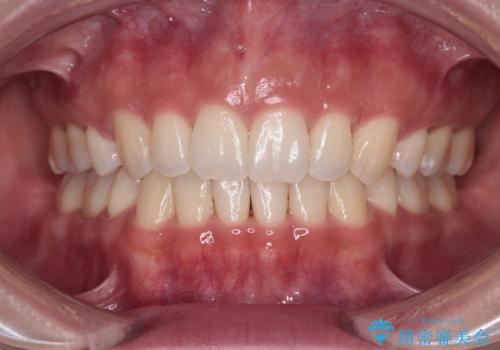

- 前歯のデコボコを治したいとのことで来院された患者様です。

上下顎ともに歯列全体の後方移動とIPR(歯と歯の間を削る)によってデコボコが解消するように設計し、インビザラインにより治療を行うこととしました。

上下ともにIPRを積極的に行っているため、舌の突出癖をしっかりと改善できないと、後戻りにより隙間やデコボコが早い段階で発現することになるため、舌のトレーニングが非常に大切になります。